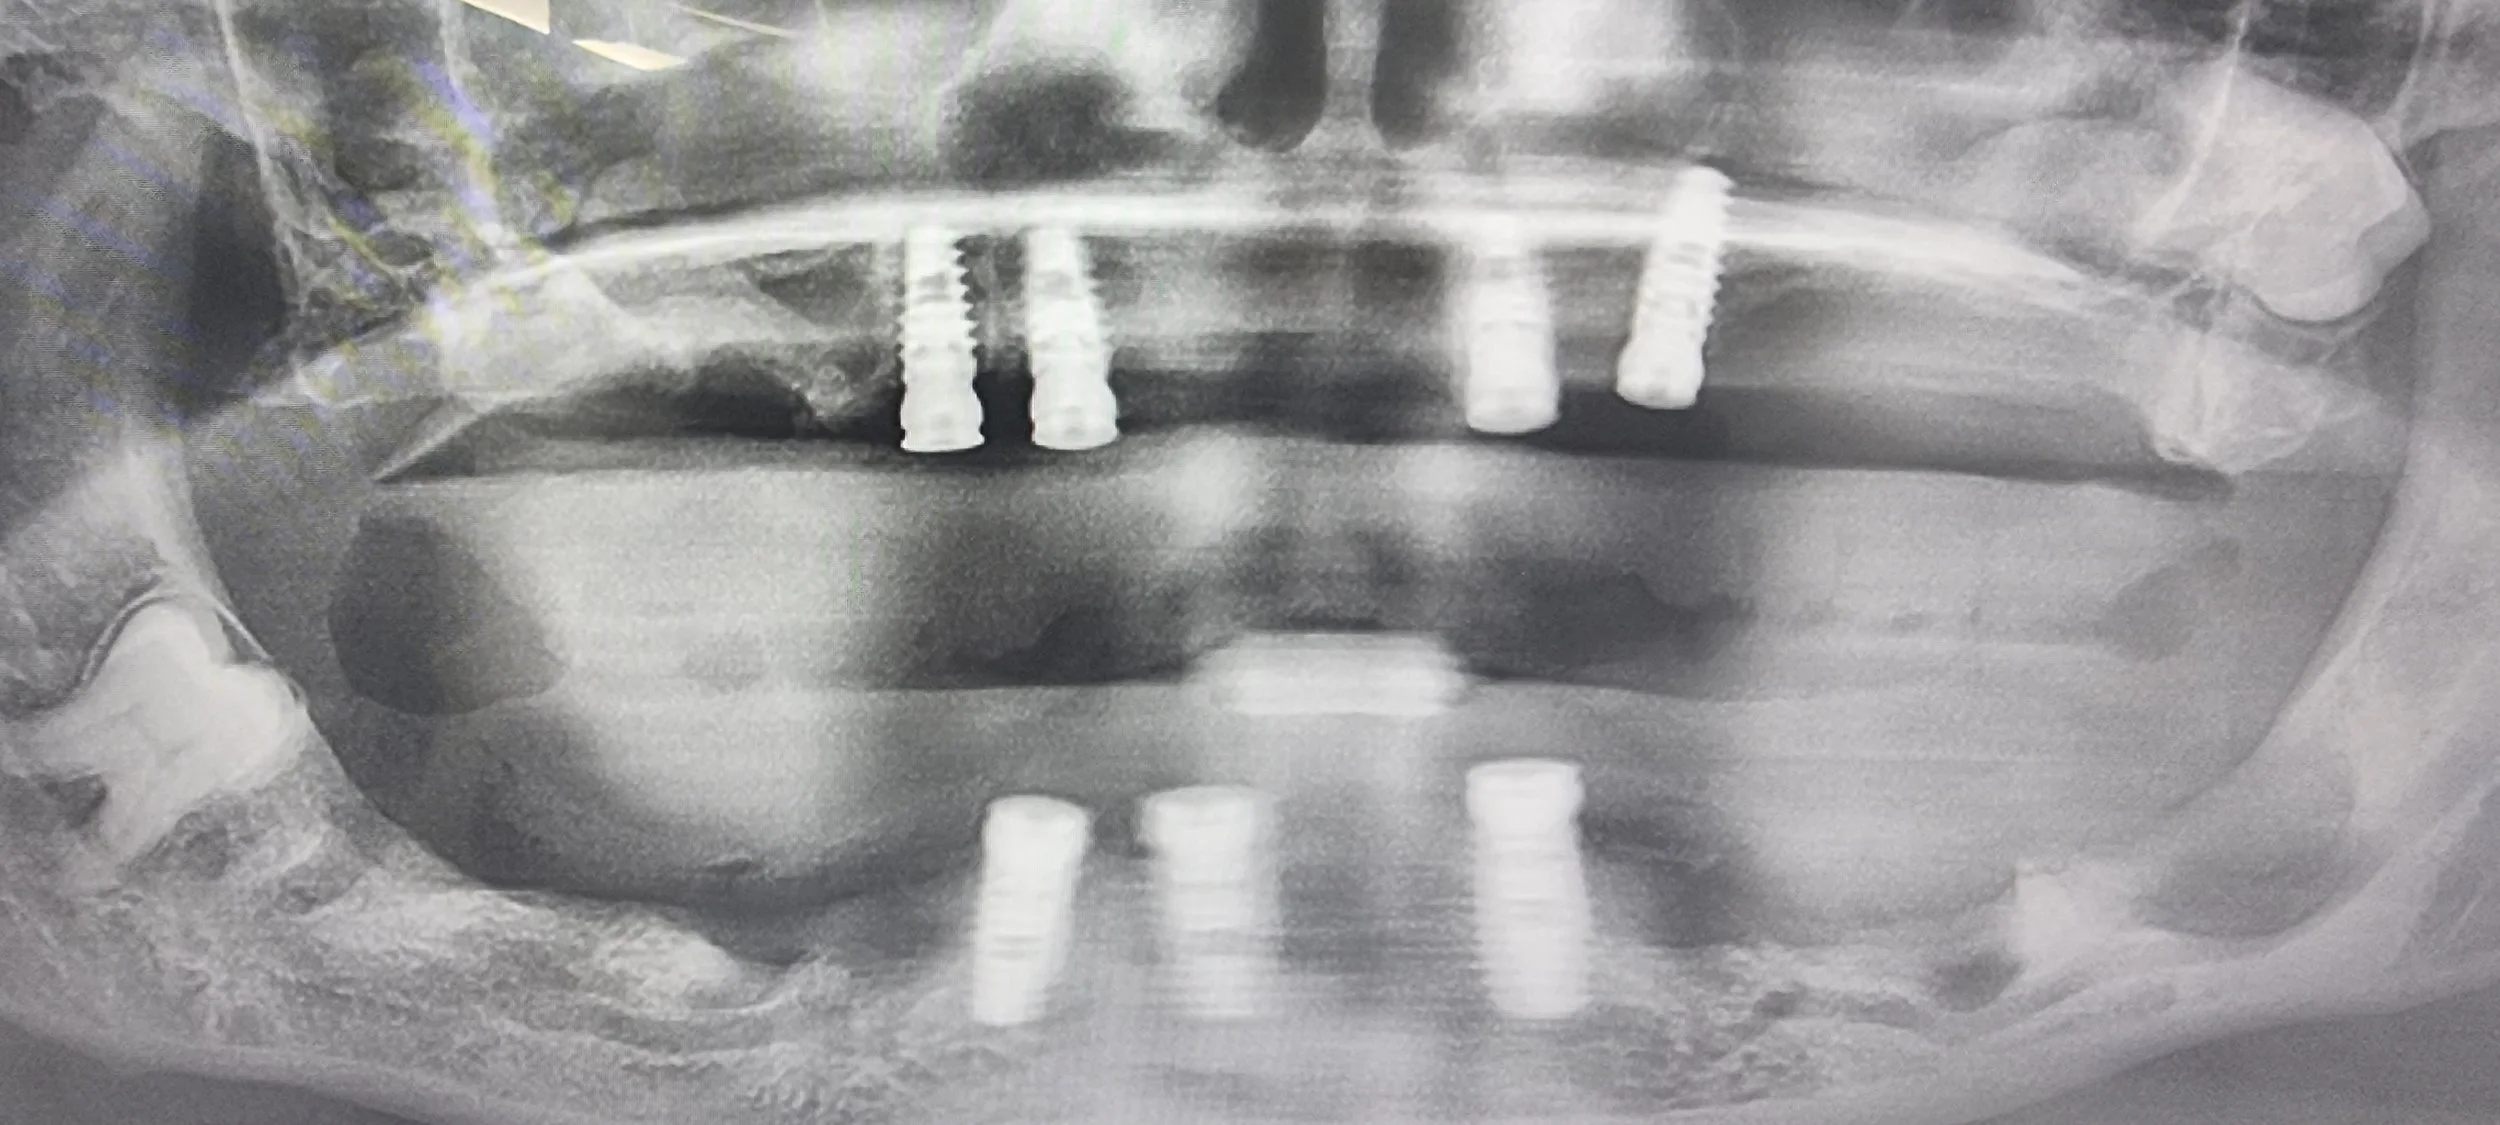

We can provide you with a new smile in just one day using the ‘All on 4/6’ implant technique. This system is one of the most advanced implant options available today and enables a full arch of teeth to be replaced with just four implants.